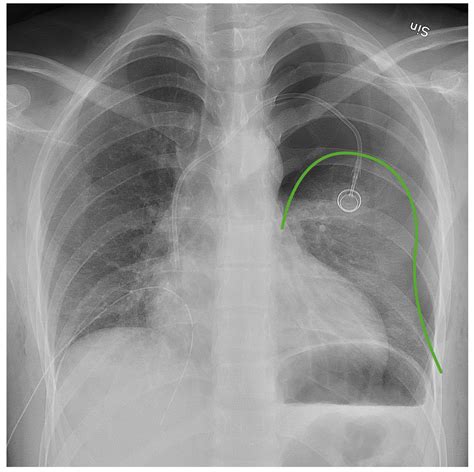

• Chest X-ray: This is often the first-line imaging study used to diagnose pneumothorax. It can detect the presence of air in the pleural space and assess the size of the pneumothorax.